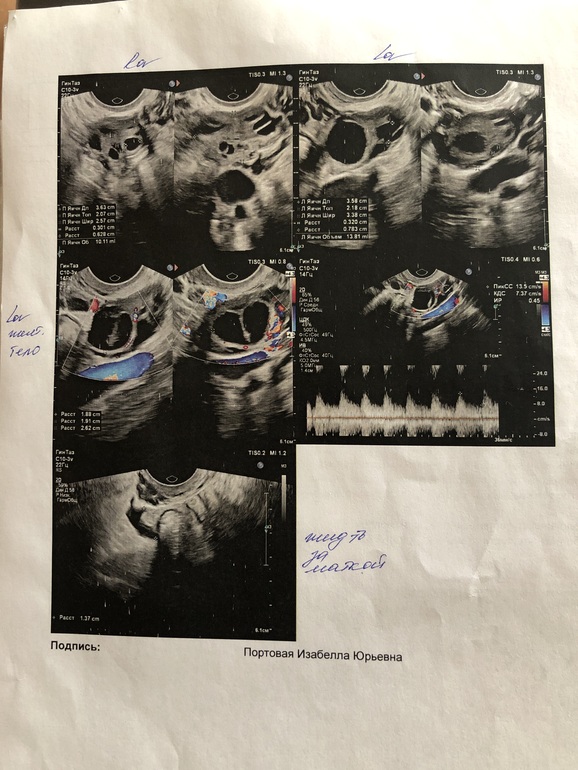

Ну а что вам не понятно в заключении. Эндометрий готов к отторжению, скоро М. По УЗИ у вас всё нормально)))

Очень интересно. Я на дату не глянула. Сколько у вас обычно цикл длится? У вас на фото эндометрий перед началом М. Структура его такая становится в этом период. То есть перед тем как он начнёт отторгаться. Получается Дюфастоном вы задержали начало М. А зачем врач дала фото именно эндометрия, а не жт?

на фото если посмотреть эндометрий, белая полоска в середине. Такой обычно за несколько дней до М. Когда сразу после О и до ,этой полосы нет .

Я лишь сужу по фото )))) Так вот по фото у вас либо не было ещё О ,либо перед М.

Ну судя по наличию жт, она все же была)